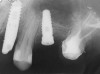

A 55-year-old male was referred for implant placement and prosthetic rehabilitation in the area of tooth No. 15. The tooth had been extracted 4 years prior. The radiograph revealed inadequate bone height for implant positioning (Figure 6). It was decided to insert an implant that was 11.5 mm in length and 3.75 mm in diameter, performing a slight osteotomic maxillary sinus lift. A heterologous bone graft also was planned to obtain a larger sinus lift.

Figure 6  Preoperative radiograph of the area around tooth No. 15.

Figure 6